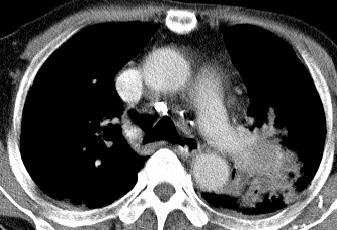

以下是引用光影相伴在2008-4-20 14:39:00的发言:[br]支持:1)左侧中央型肺癌伴左肺上叶阻塞性肺炎。、[br] 2)双侧少量胸腔积液。

以下是引用xianxianzhongyi在2008-4-20 14:44:00的发言:[br]本人愚见:次病例短短两月的时间,呈现如此大面积实变,病变增长过于迅速,此其一。其二,病变在动脉早期既有明显强化。其三,左上叶后段及下叶背段多叶受累。其四,肺门及纵隔内未见明显肿大的淋巴结。估计层面较厚段支气管显示不清。 诊断:炎性实变可能性大。